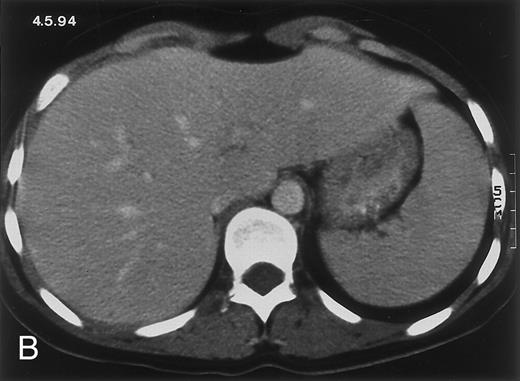

(D) On August 23, 15 days after the neutrophil count had dropped below 500/μL in the third chemotherapy cycle, focal liver lesions clearly decreased in size and number. (E) On September 30, 35 days after neutrophil recovery, multiple hepatic abscesses are seen (arrowhead). To show maximal extent of lesions the scan shown is at a slightly different level. (F) On June 16, 1994, 230 days after neutrophil recovery, the CT scan has normalized.